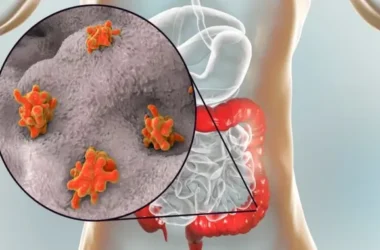

وجود مخاط في البراز

على الرغم من أن وجود كمية صغيرة من المخاط في البراز يُعد أمرًا طبيعيًا، إلا أن المصابين بالقولون العصبي غالبًا ما يلاحظون زيادة ملحوظة في كمية المخاط. هذه الزيادة قد تكون مصدر قلق وتؤكد على نشاط القولون العصبي.